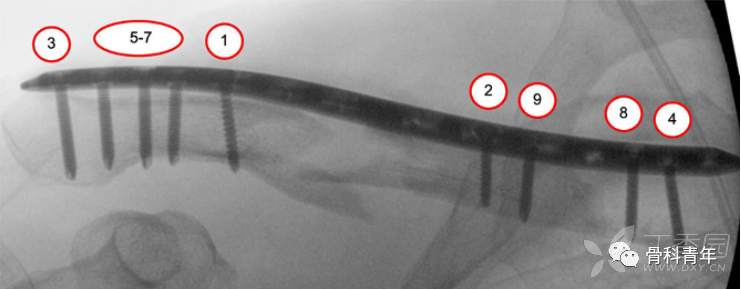

4.螺钉置入与最终确切固定

在临时固定复位满意后,经钢板远近端最靠近骨折块的钉孔,置入一枚皮钉。如此时骨折块存在成角或移位,可经复位钳夹持复位。复位后两边钉孔依次置入锁定螺钉桥接固定。

螺钉的置入顺序。